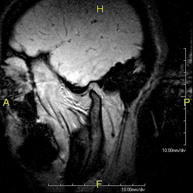

- RM Cerebral (craneal)

Prueba diagnóstica no invasiva que consiste en la obtención de imágenes de alta definición anatómica del cerebro mediante el empleo de un campo electromagnético y ondas de radio (con un emisor y un receptor). No utiliza radiación ionizante. Indicaciones: problemas vasculares, pérdida de memoria, epilepsia, cefalea, malformaciones, sospecha de tumor, meningitis. - RM Cais